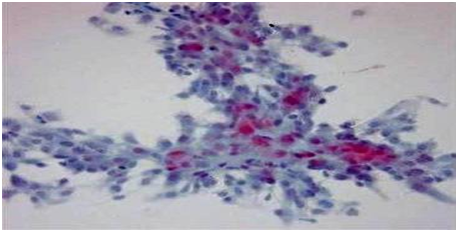

Grossly, pigmented villonodular synovitis appears as a proliferative synovial process with brownish villo-nodular fronds in the affected joints (Figure 3).2 Multiple yellow to brown nodules could be detected in localized types and in the pes anserine bursa (Figure 4). Histopathologically, the tumor is generally represented by many mononuclear histiocytic cells and irregularly interspersed multinucleated giant cells. Hemosiderin pigments could also be detected. Some foamy histiocytic cells may individually interspersed or form clusters (Figure 5).8 Osseous, cartilaginous, and soft tissue involvement was also seen .Fine needle aspiration cytology reveal a few clustered and scattered plump spindle cells containing hemosiderin-pigments and several scattered multinucleated giant cells (Figure 6).

Figure 6 Smear showing a few clustered and scattered plump spindle cells containing hemosiderin pigments (Papanicolaou staining ×400).